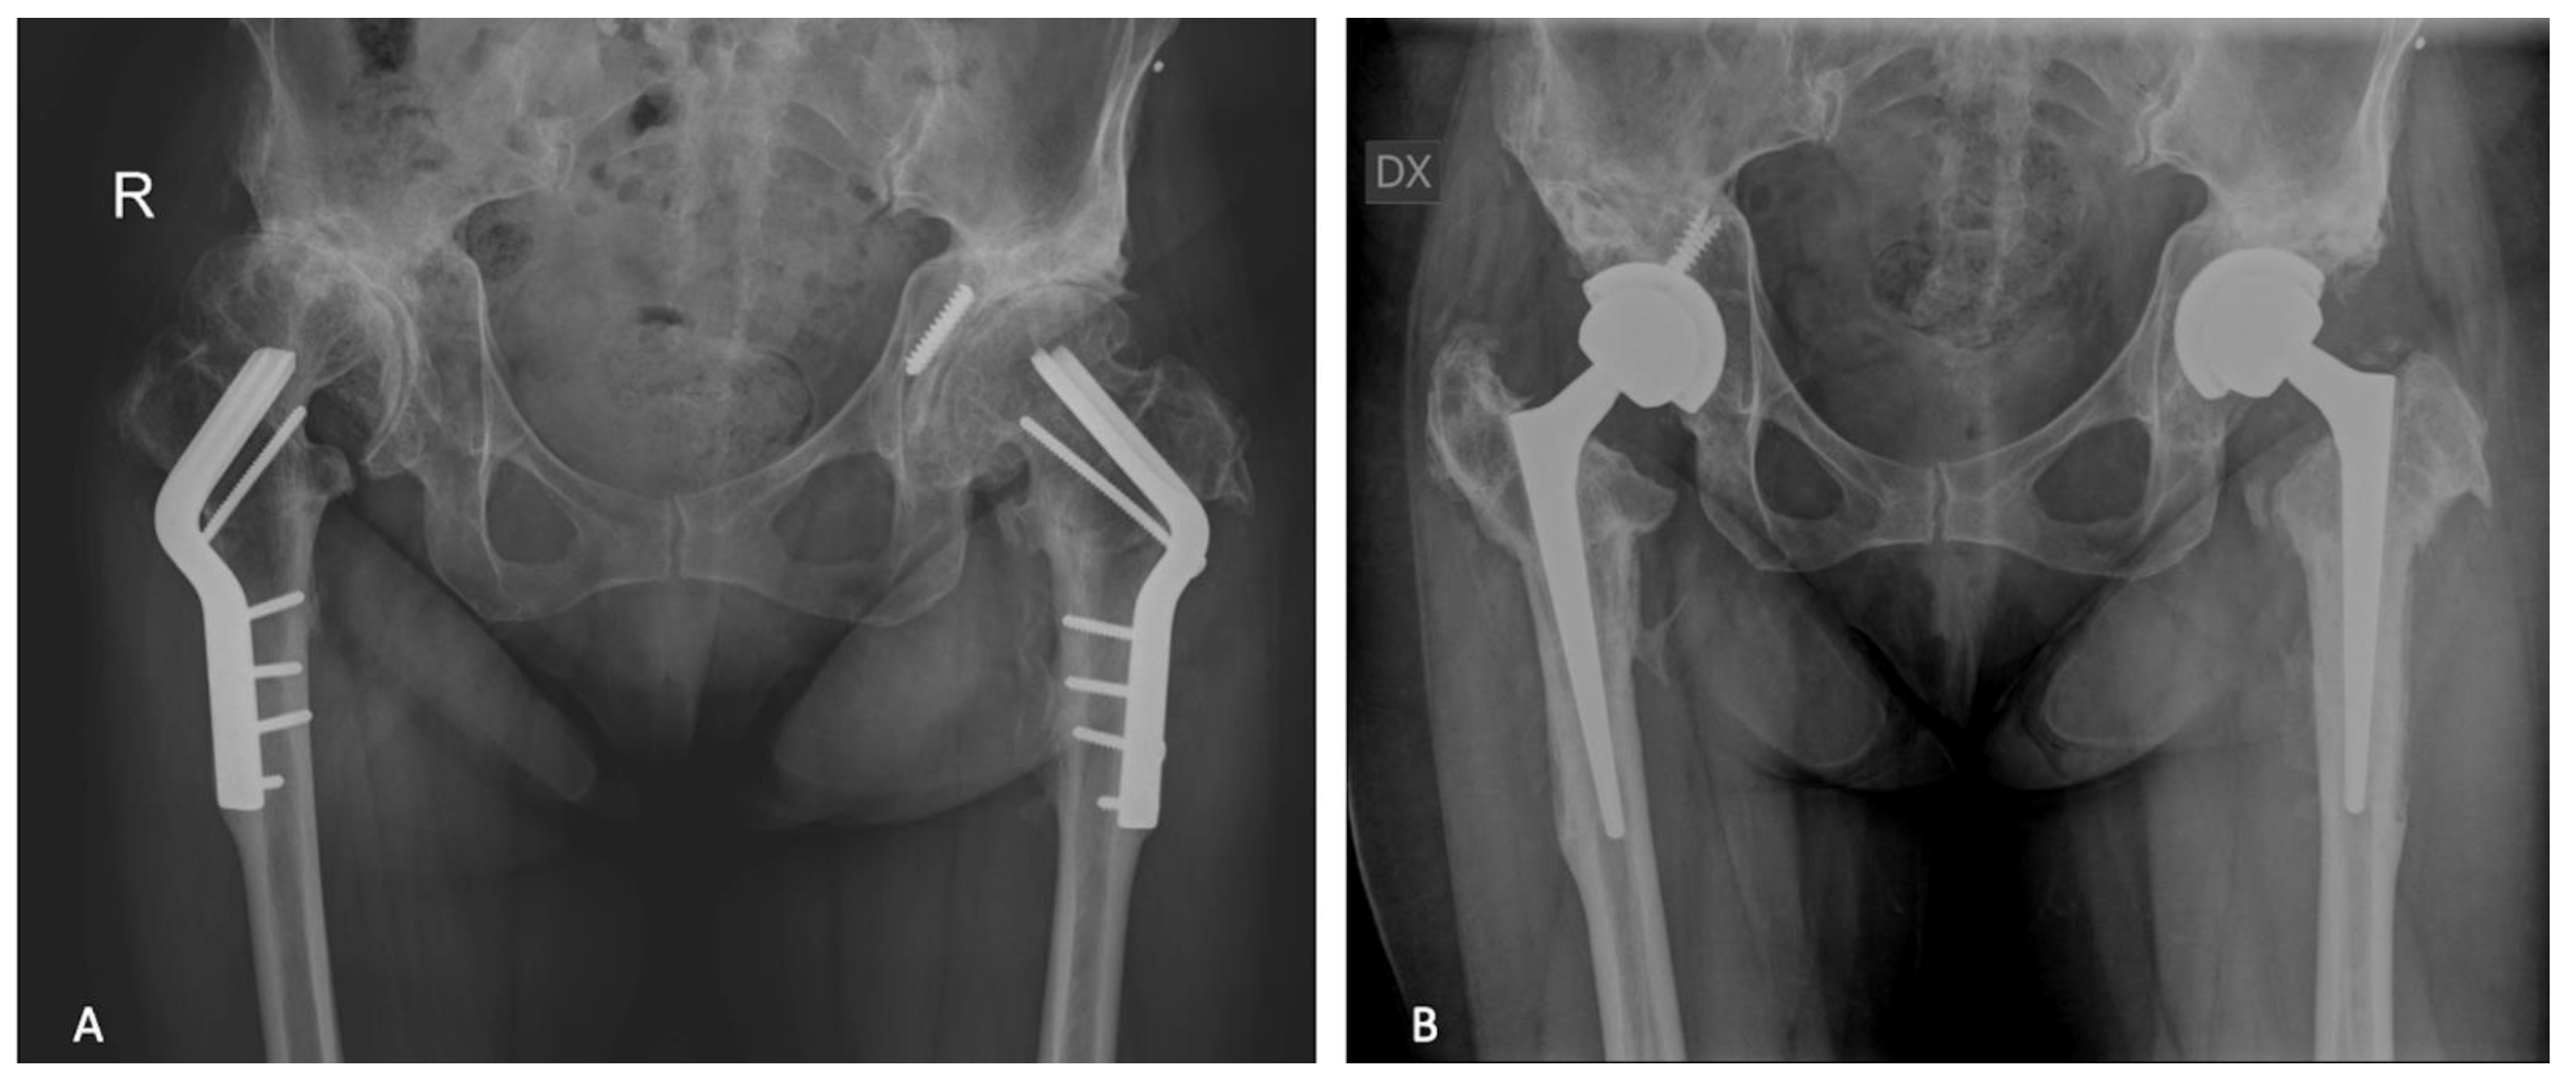

2.1. Surgical Procedure